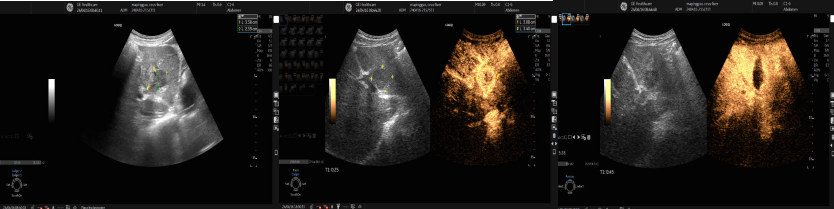

一名72岁的患者疑似肝脏深部小肿瘤(大小9x8mm),因肿瘤较小,位置较深,且紧贴肝静脉,穿刺难度及风险较高。魏炜教授术前缜密规划穿刺点和穿刺路径,巧妙避开肝内血管,精准取材,病理诊断:肝组织及增生纤维组织内见中分化腺癌浸润转移,结合免疫组化染色结果及病史,考虑胃癌转移可能,为临床的下一步治疗提供可靠的依据。

疑似肝脏深部小肿瘤的超声引导下穿刺活检及穿刺病理结果

魏教授进行超声引导下经皮肝脏穿刺活检